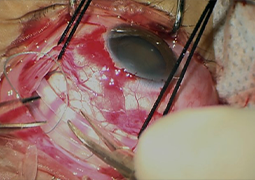

- Postradiačná makulopatia u pacientov s malígnym melanómom corpus ciliare a chorioidey po stereotaktickej rádiochirurgii